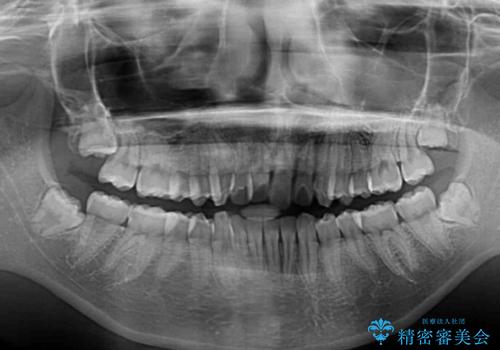

- 就職するまでに歯並びをきれいにしたいとのことで来院された患者様です。

前歯の叢生を気にしていましたが、極力突出感を改善できるようにすることとし、インビザラインにて矯正治療を行うこととしました。